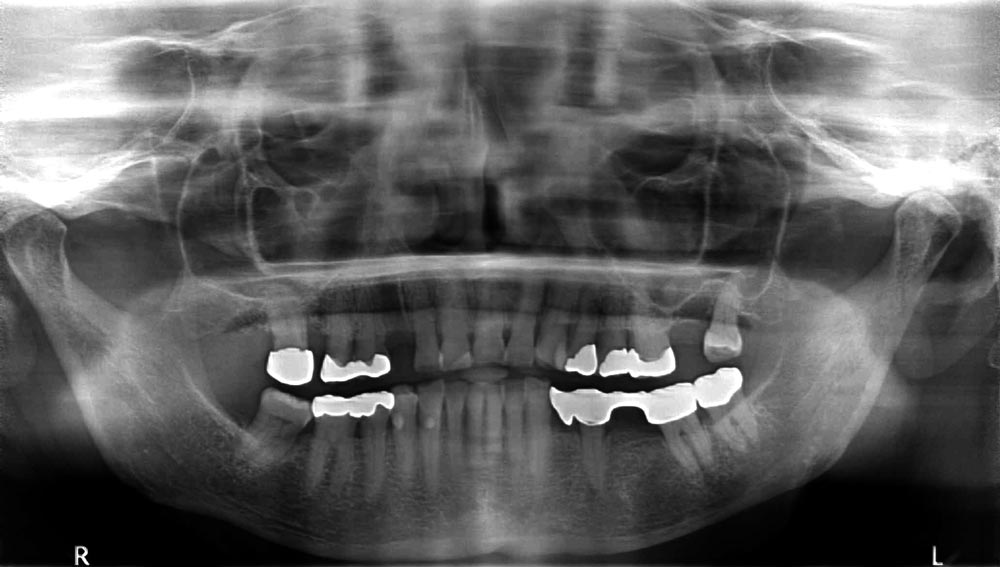

04/12 - Preoperative radiological situation

Block augmentation with maxgraft® in the maxilla - PD Dr. Dr. F. Kloss